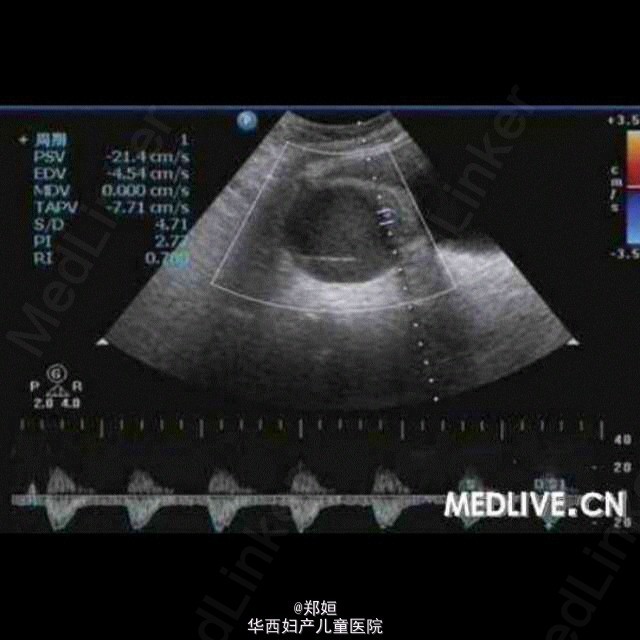

病历资料:女,34岁,6年前体检发现左附件区有一直径为2 cm的肿物,因肿物体积较小而未治疗。5年前患者无明显诱因地出现月经期腹痛 ,伴腰酸腹胀逐渐加重,须服止痛药缓解,B超复查显示,盆腔肿物体积增大。超声检查:子宫肌层回声欠均匀,子宫后壁肌间隐约可见3.8 cm×3.5 cm×3.7 cm中等回声包块,边界欠清,点状血流信号(图1)。右附件可见6.7 cm×5.8 cm×5.3 cm囊性包块,边界清,外形规则, 内为液性暗区伴细密光点,囊壁可见点状血流信号(图2和图3);子宫左上方可见6.1 cm×4.5 cm×4.6 cm囊性包块,边界清,外形尚规则 ,内为液性暗区伴细密光点,内可见分隔,隔壁可见条状血流信号(图4)。 诊断:子宫增大;子宫腺肌症;双附件区囊性包块。 术中所见:子宫前位,宫体球形,质硬;子宫后壁外突瘤核,界限不清。双侧卵巢均囊性增大,囊肿内为巧克力样物质,均为多房,与阔韧 带后叶、乙状结肠和子宫后壁粘连。 http://case.medlive.cn/obgyn/case-article/show-46213_207.html